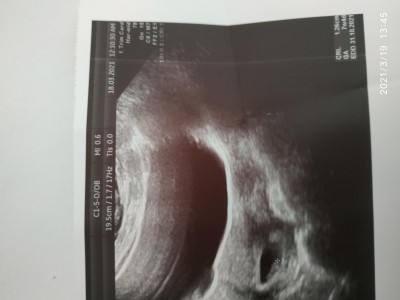

baktım ama anlayamadım 7 haftalık hamileyim

Gebelik haftası 7+4

Aşağıda sagda köşede crl yazıyor.1.26 cm bebegin

Crl yazan yerdir ,resim biraz bulanık ama sanki 1.26 cm yazıyor

Crl 1.20 cm yazıyor

Crl 1.26 cm yazıyor

Ultrason kağıdının alt tarafında crl yazan yer var orası ortalama boyutu gösteriyor yanlış görmüyorsam 1.26 cm yazıyor canım benim de o kadardi doktorum öyle söylemişti :)